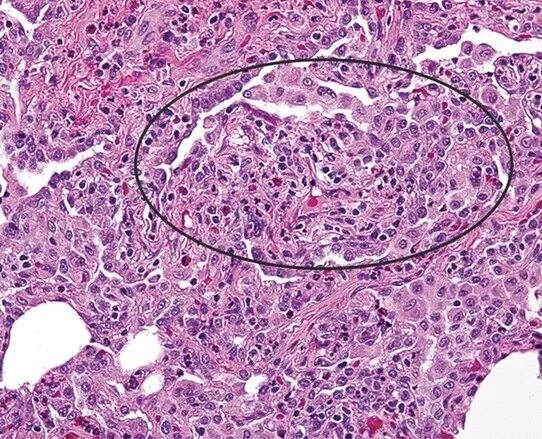

Инфильтрация в гистологии